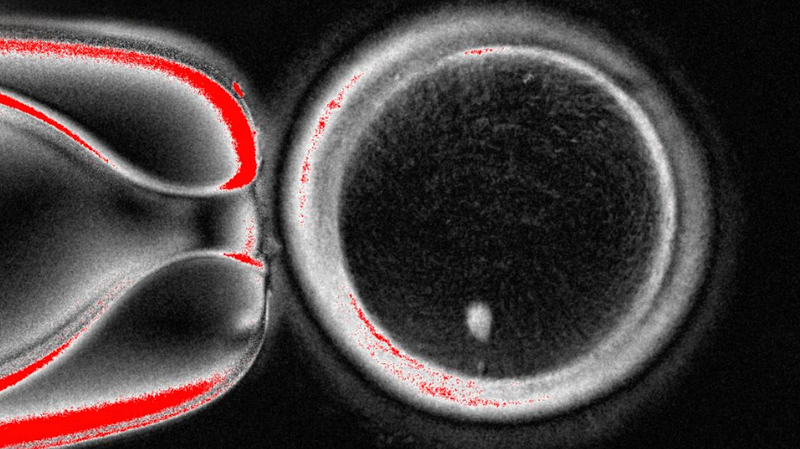

Científicos convierten células de la piel en óvulos humanos en un avance de laboratorio

Investigadores emplean mitomeiosis para transformar células de la piel en óvulos humanos funcionales, allanando el camino para nuevos tratamientos de fertilidad.

Investigadores emplean mitomeiosis para transformar células de la piel en óvulos humanos funcionales, allanando el camino para nuevos tratamientos de fertilidad.